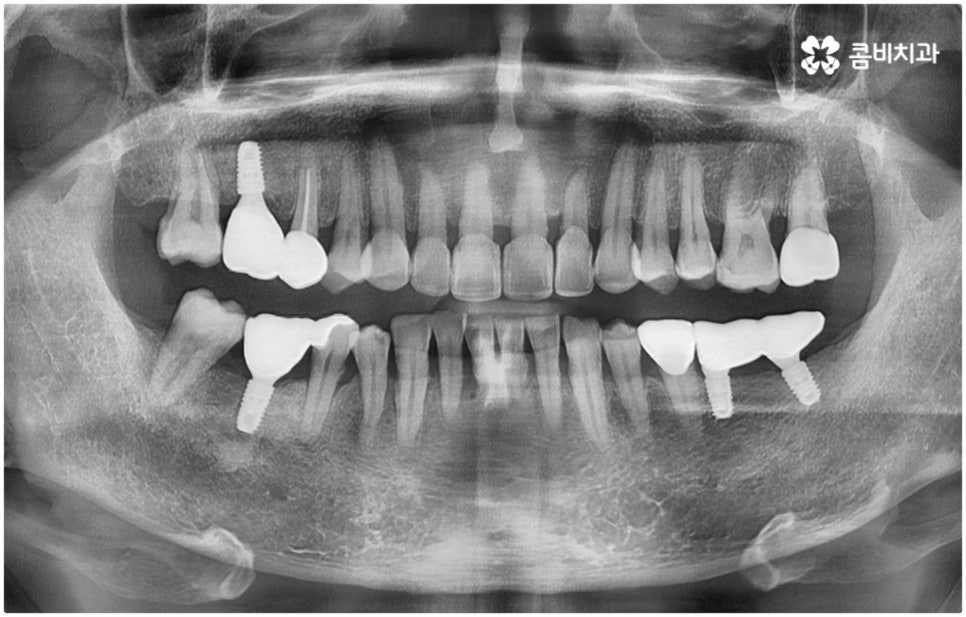

관련 기술의 발달 및 꾸준한 학술 연구를 통해 양질의 임상 데이터가 쌓이고 국산 임플란트 재료가 개발되어 비용적인 부담이 줄어들면서 점차 대중화되기 시작한 임플란트는 현재 치아 상실에 대처하는 가장 대표적인 방법으로 손꼽히고 있어요. 그러나 각각의 상황에 따라 6~8개월, 길게는 1년 까지도 소요될 수 있는 임플란트 시술 기간은 바쁜 현대인들에게 부담으로 다가올 수 있는데요. 업무 등으로 시간 여유가 넉넉하지 않은 경우 임플란트 치료 자체를 망설이는 원인이 되기도 할 거예요. 이럴 때는 발치후 임플란트 즉시 식립 방식을 고려해 볼 수 있어요.

발치후 임플란트 즉시 식립 방식은 다른 임플란트와 달리 치아가 탈락한 빈 자리에 곧바로, 또는 조금 남아있던 뿌리를 뽑은 후 그 자리에 그대로 임플란트를 심기 때문에 공백 기간이 단축될 수 있고 임시치아 제작을 통해 해당 기간 동안 임시 틀니를 사용해야 하는 데서 오는 불편함 및 심미적인 어색함도 해결할 수 있어요. 또한 환자분들의 입장에서 마취 한 번에 발치와 식립 두 가지 과정이 함께 이뤄지기 때문에 통증과 두려움이 감소되고 치과에 내원해야 하는 횟수도 줄어들어 번거로움이 덜 할 수 있습니다.

치아가 빠진 순간부터 이를 받치고 있던 치조골이 서서히 흡수되기 시작하므로 영구치가 빠지고 나서 시간이 많이 지나게 되면 부족한 잇몸뼈 부분을 뼈이식으로 보충해 주는 과정이 추가적으로 들어가야 하지만 이미 뼈가 손상된 경우가 아니라면, 즉시 식립을 하면 그럴 필요가 없는 거예요. 또한 잇몸이 이미 내려앉은 후 수복을 하려면 잇몸 라인이 인위적으로 만들어질 가능성이 높아지는데 치조골 소실이 크게 일어나기 전에 임플란트를 심게 되면 주변 치아 및 잇몸과 보다 조화롭게 맞출 수 있어서 심미적인 부담도 덜 수 있어요.

발치후 임플란트 식립까지 회복 기간을 두지 않고 즉시 심게 되면 원래 치아가 있던 자리를 육안으로 확인한 후 그 자리에 곧바로 식립하므로 보다 정확한 위치를 잡을 수 있다는 장점도 있습니다. 하루 만에 식립과 임시치아까지 장착이 가능하여 간단한 식사도 할 수있다는 점에서 원데이 임플란트라고도 불리는 즉시 식립 방식은 지금까지 알아본 바와 같이 여러 장점을 가지고 있기 때문에 많은 분들이 선호하시고 있는데요.

하지만 여기서 주의하셔야 할 점은 누구나 발치후 임플란트 를 즉시 식립할 수 있는 것이 아니라 바탕이 되는 잇몸뼈의 양이 충분하고 기존에 염증과 같은 잇몸 질환이 없는 분들의 경우에만 이용할 수 있는 방법이기 때문에 3D CT 등 정밀 분석 기계로 환자분들의 상태를 정확하게 진단한 후에 결정해야 한다는 거예요.

즉, 해당 분야의 임상 경험이 풍부한 숙련된 의료진분들이 계신 치과에서 자신이 발치후 임플란트 즉시 식립 방식이 가능한지 부터 확인하실 필요가 있는데요. 만약 다양한 이유로 인해 발치 후 즉시 심는 것이 불가능한 케이스라고 한다면 상황에 맞게 뼈이식, 상악동 거상술, 잇몸 질환 치료 등 선처치들을 먼저 해 주고 나서 충분한 회복 기간을 두고 임플란트 시술을 진행해야 식립 성공률 및 지속 가능성을 높일 수 있습니다. 이렇게 환자분들 각각의 상황을 고려하지 않은 채 발치 후 즉시 식립을 무리하게 진행하게 되면 임플란트의 위치를 제대로 고정하는 데 어려움이 있어 해당 치아로 잘 씹을 수 없게 되고 얼마 지나지 않아 다시 쓰러지거나 주변 치아와 잇몸에 압박을 가해서 지속적으로 좋지 않은 영향을 주게 되는 등 문제가 커질 수 있으니 주의하실 필요가 있어요.

임플란트 후 수명을 늘리는 방법에 대해서 문의를 주시는 분들이 많이 있는데요. 지속성을 높이려면 말씀드린 것처럼 치료 자체의 정확성을 신경쓰는 것이 우선시 되어야 할 거예요. 즉 환자분들의 상황을 꼼꼼하게 검진하고 이에 맞는 방법으로 정확하게 식립하는 치과에서 임플란트 수술을 진행하는 것이 무엇보다 중요하다고 할 수 있습니다. 이를 위해서 환자분들의 잇몸뼈 두께나 밀도를 면밀하게 살필 수 있는 3D CT 기계를 갖추고 처음부터 끝까지 책임 진료하는 숙련된 의료진 분들과 함께 하시는 게 좋을 거예요.

이때 환자분들 각각의 정밀한 맞춤 계획을 세우고 이를 무리하지 않게 진행하기 위해서는 해당 치아의 잇몸뼈 상황 뿐 아니라 주변 치아 구조, 신경 위치 그리고 환자분들의 전체적인 구강 내 건강 상태 (치주 질환 여부 등) 를 자세하게 관찰하고 그 밖에 연령이나 기존 전신 질환 여부 (상용하는 약이 있는지 여부도 포함) 등 모든 부분을 충분한 상담을 통해 빠짐없이 파악하며 행여 중간중간 돌발 상황이 발생해도 침착하게 해결해 나가는 것이 중요하기 때문에 담당 의료진에게 굉장히 높은 수준의 기술력과 풍부한 노하우가 요구됨을 짐작할 수 있는데요. 이와 같이 매우 고난도 진료인 발치후 임플란트 시술을 보다 안정적으로 진행하기 위해서는 정밀 장비 보유 여부 및 의료진의 경력과 노하우를 철저하게 체크해 보시고 치과를 신중하게 선택하실 필요가 있어요.